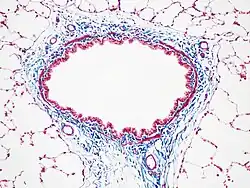

Masson-Trichrom-Färbung

Masson-Trichrom-Färbung von Lungengeweben der Ratte, mit Bindegewebe (blau), Zellkernen (rot/lila) und Zytoplasma (rot/rosa)

Die meisten Varianten der Masson-Trichrom-Färbung erzeugen rot gefärbtes Keratin und Muskelfasern, blaues oder grünes Kollagen und Knochen, rosa Zytoplasmata und braun-schwarze Zellkerne.